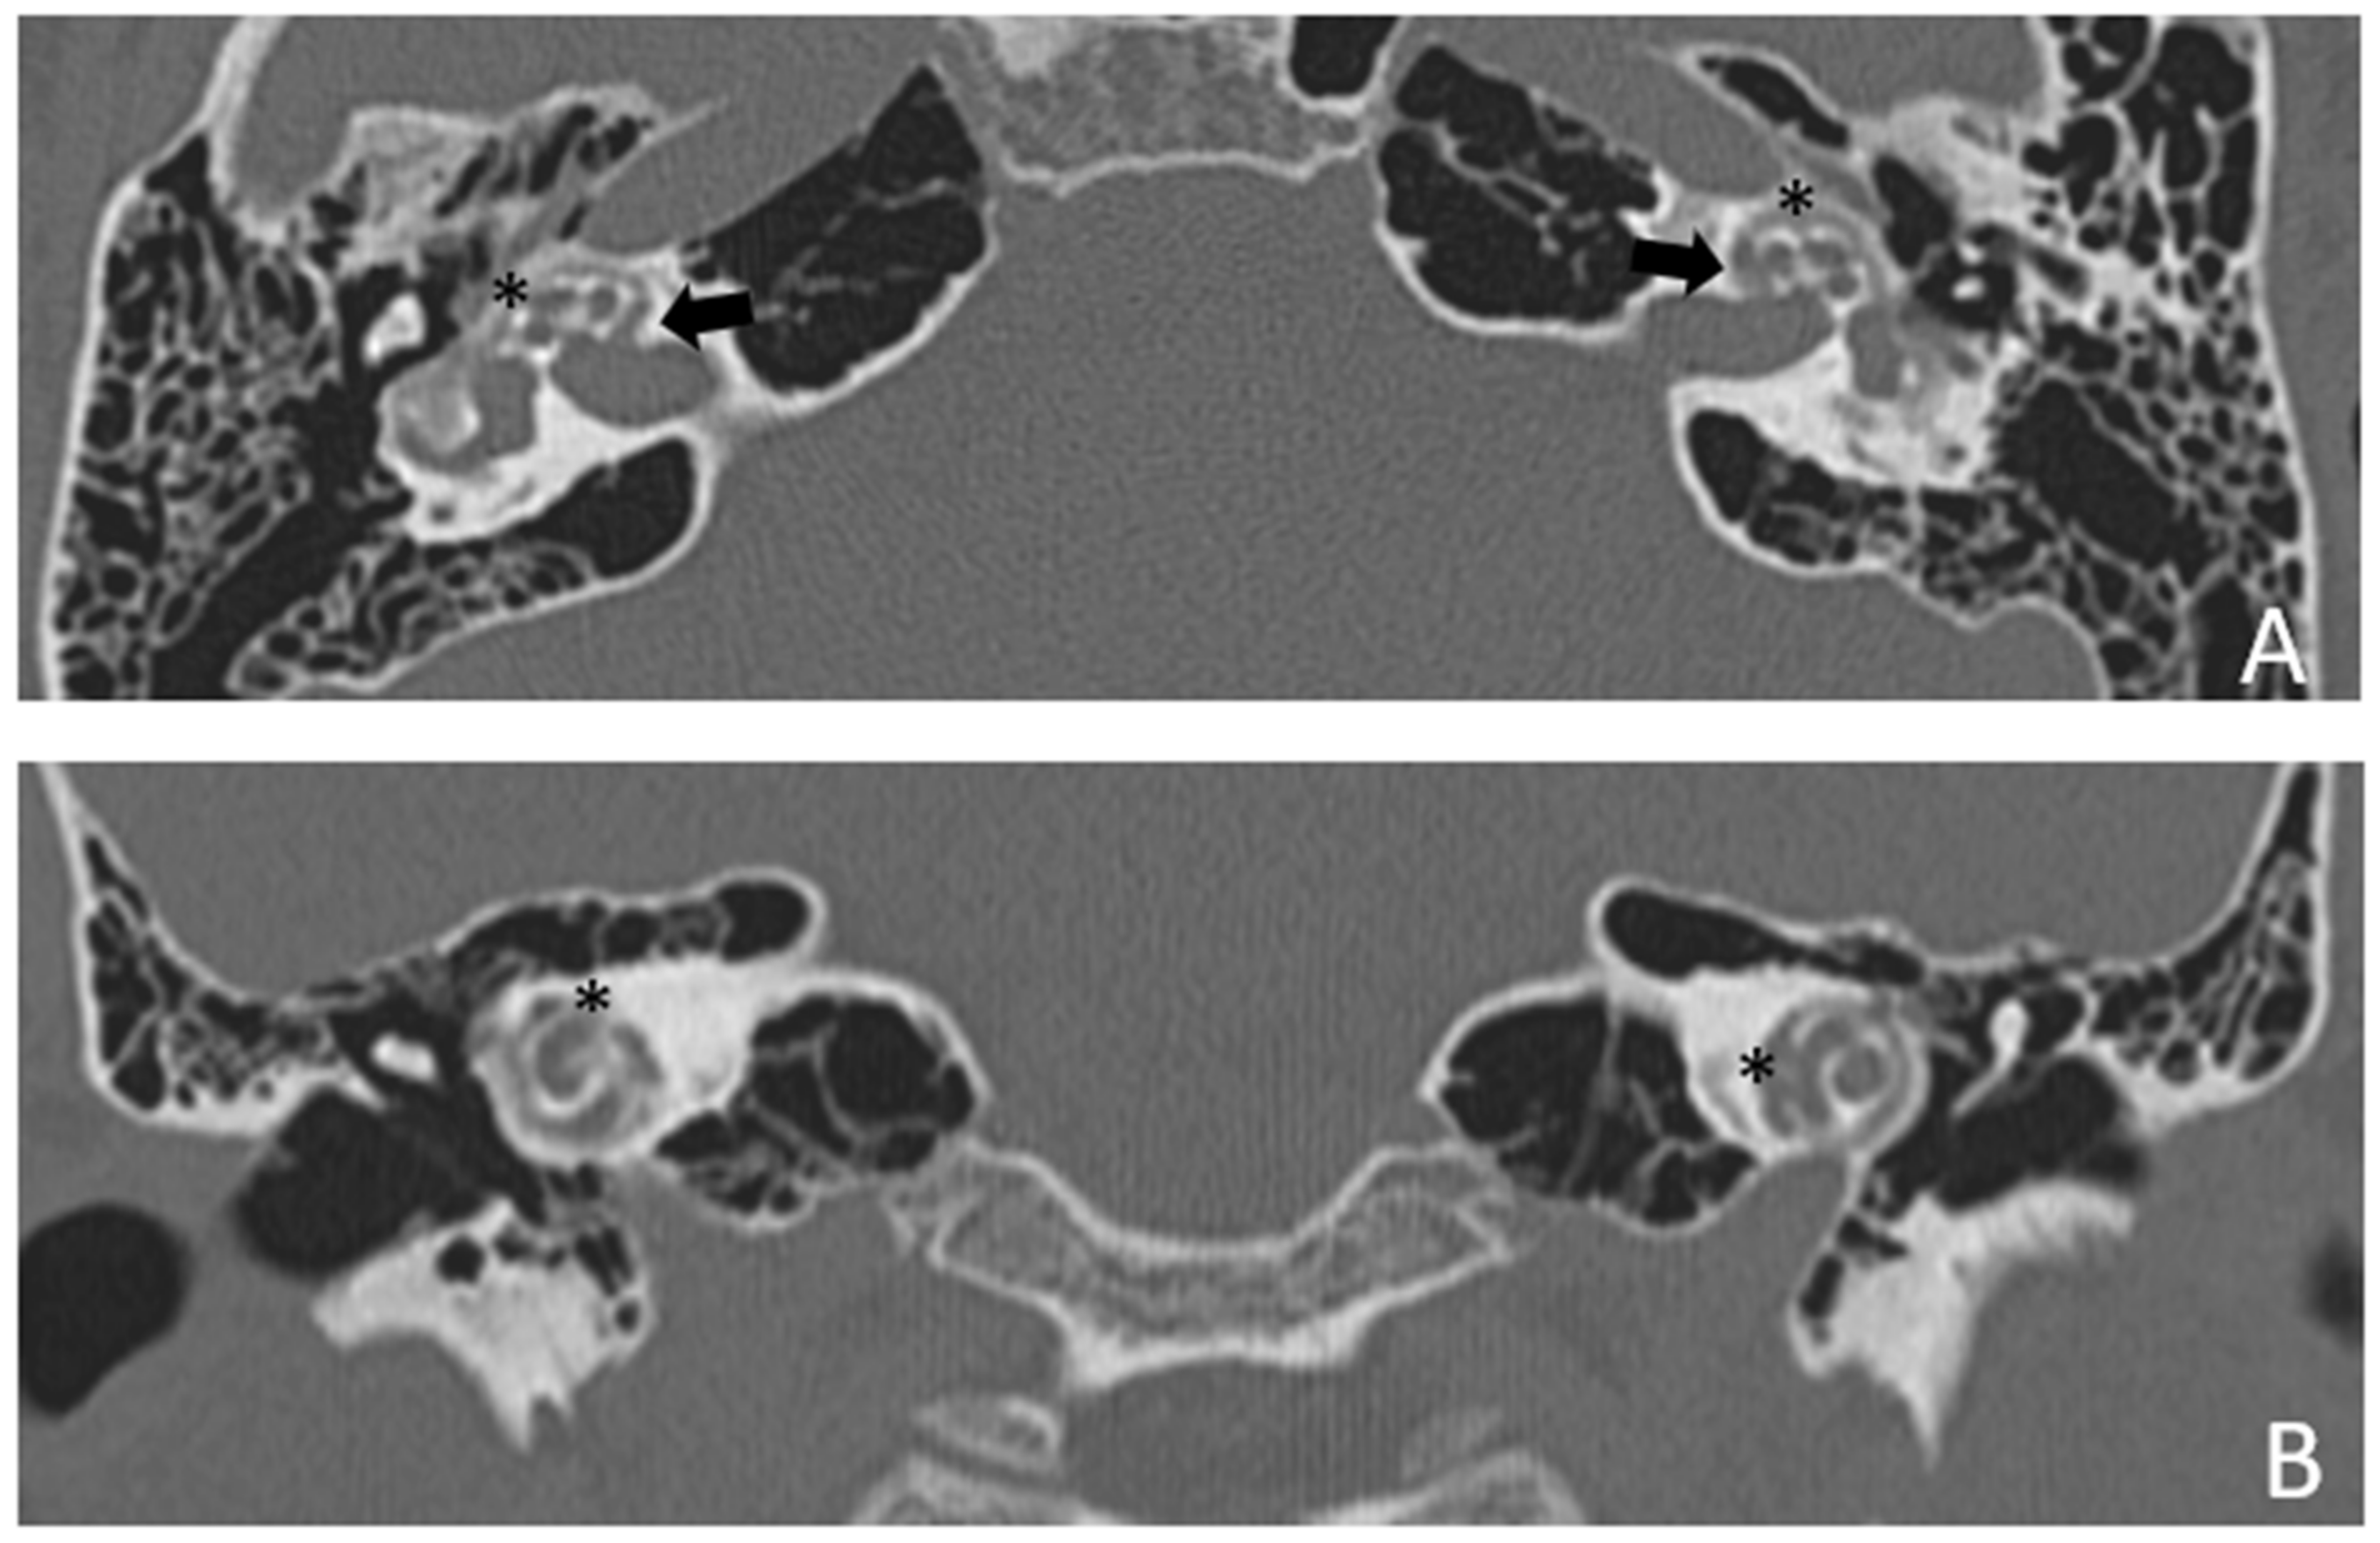

Patient #3, affected by otosclerosis: HL started as mild CHL, but she had a progression with a worsening of the bone threshold, probably due to cochlear evolution of the disorder. Even in this case, there was no indication for stapes surgery because of the communication between CSF and perilymph through the cavities. The images also show a superior semicircular canal deiscence (SSCD)on the left. CT and MR images show the bilateral cavities (Figure 5 and Figure 6).

Figure 5. CT images of patient #3 with bilateral otosclerosis and SSCD of the left ear. (A,B), axial plane; (C,D), coronal plane. A cavitating osteorarefation around the cochlea is clearly visible. The communication of the cavity with the cochlea is indicated by asterisks. The arrow indicates the origin of the cavity from the IAC. The circle indicates the dehiscence of the SSC on the left side.